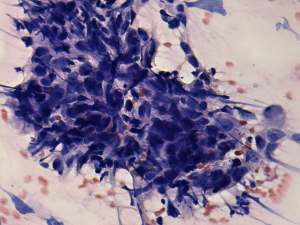

Cytological diagnosis: anaplastic carcinoma.

Histopathology: anaplastic carcinoma.